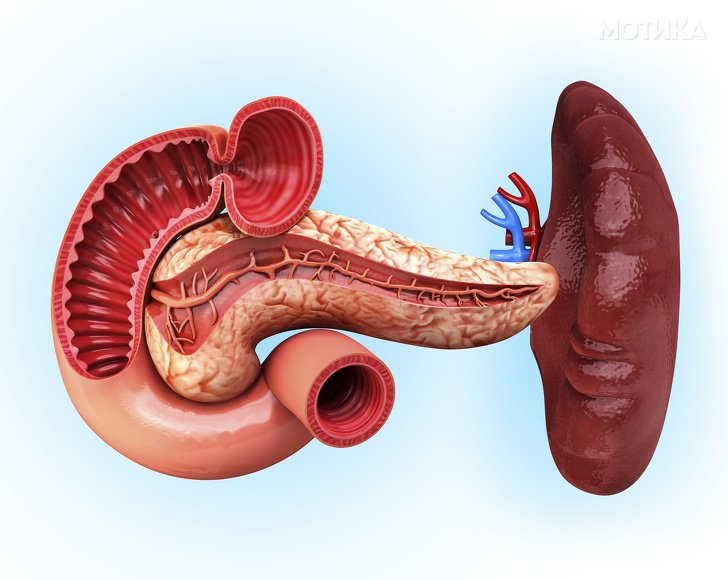

10. Панкреас

- Панкреасот има опашка и глава.

- Би можеле да живееме без него, но тоа не би било забавно бидејќи, иако храната никогаш не оди во овој орган, тој игра клучна улога во варењето со ензимите што ги ослободува.

- Има рецептори за вкус кои можат да детектираат шеќер, но не ги испраќа сигналите до мозокот, како што го прават тоа пупките за вкус на вашиот јазик. Наместо тоа, ја користи оваа детекција за да ги балансира хормоните.